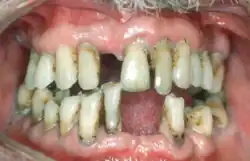

Periodontal disease, also known as gum disease, is a set of inflammatory conditions affecting the tissues surrounding the teeth.[5] In its early stage, called gingivitis, the gums become swollen and red and may bleed.[5] It is considered the main cause of tooth loss for adults worldwide.[7][8] In its more serious form, called periodontitis, the gums can pull away from the tooth, bone can be lost, and the teeth may loosen or fall out.[5] Halitosis (bad breath) may also occur.[1]

Periodontal disease typically arises from the development of plaque biofilm, which harbors harmful bacteria such as Porphyromonas gingivalis and Treponema denticola. These bacteria infect the gum tissue surrounding the teeth, leading to inflammation and, if left untreated, progressive damage to the teeth and gum tissue.[9] Recent meta-analysis have shown that the composition of the oral microbiota and its response to periodontal disease differ between men and women. These differences are particularly notable in the advanced stages of periodontitis, suggesting that sex-specific factors may influence susceptibility and progression.[10] Factors that increase the risk of disease include smoking,[4] diabetes, HIV/AIDS, family history, high levels of homocysteine in the blood and certain medications.[1] Diagnosis is by inspecting the gum tissue around the teeth both visually and with a probe and X-rays looking for bone loss around the teeth.[1][11]